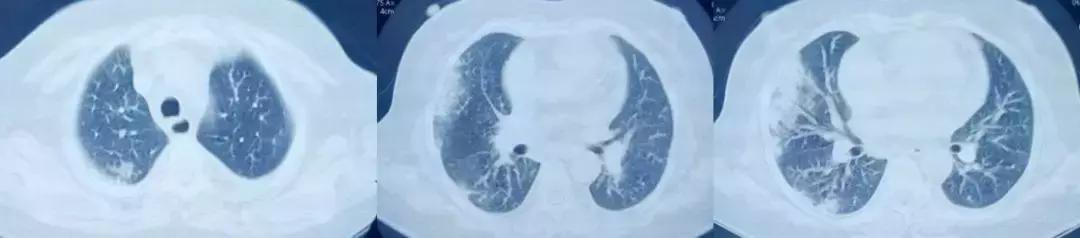

您能根据影像判断患者是病毒感染吗?但是在广谱抗生素抗感染治疗无效的ARDS患者,一定警惕病毒感染。

男,67岁,急性病程;发病前有旅游病史;主诉:发热、干咳伴呼吸困难2天,加重1天;查体:体温38.3℃,心率96次/分, 呼吸35次/分,血压98/63mmHg,SpO2 88%(FiO20.37),急性病容,呼吸急促,左肺呼吸音粗,右下肺呼吸音减弱,双下肺可闻及湿啰音;肺部CT示双下肺渗出、实变影,动脉血气分析提示I型呼吸衰竭。

2017-9-26

2017-9-29